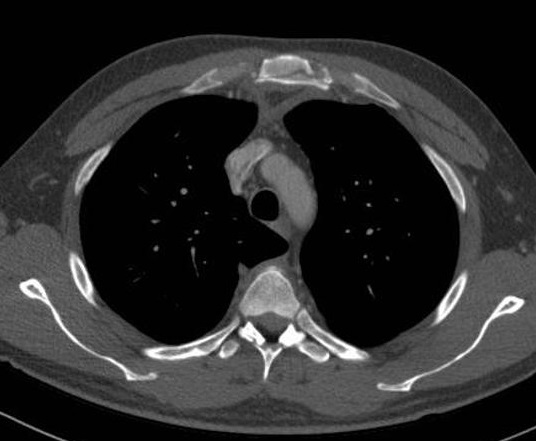

Image radiologique TDM en

coupe axiale fenetre parenchymateuse d'une

fracture de plusieure de cote anterieure ( 3th -9th

) en formant " flait chest " de la poitrine . |